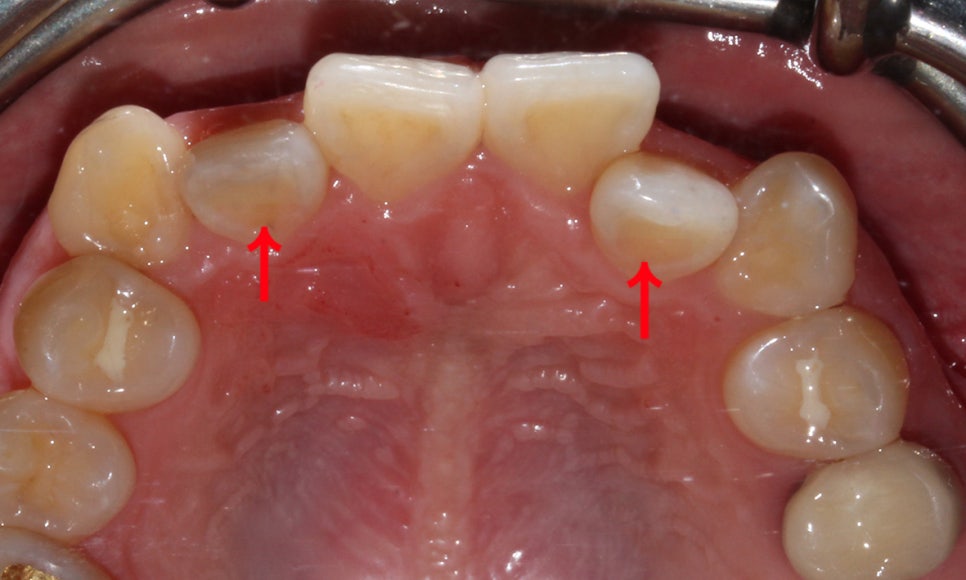

하악의 경우에도 전치부의 치열이

삐뚤삐뚤한 모습을 확인할 수 있는데요,

송곳니덧니 Case에서 전체적인 안모의 형태가

이상적인 안모의 모양인 U-라인을

그리지 못하는 모습으로 전체교정을 통해

치열을 바로잡고 삐뚤어진 안모의 모양을

바로잡는 교정 계획을 수립하였습니다.